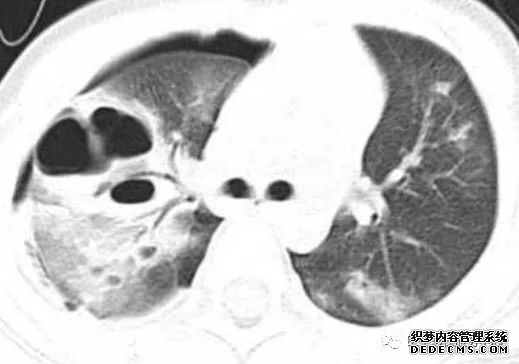

张力性纵隔气肿影像表现及严重度分级